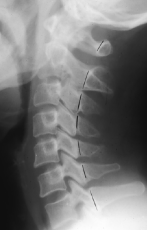

Q what is the name of this measurement? and what is the average + range?

A: Posterior Cervical Line

assesses for a smooth, arc-like curve of the spinolaminar junctions. No average or range is specified, but significance in children notes the C2 junction should not be more than 2 mm anterior to the line.